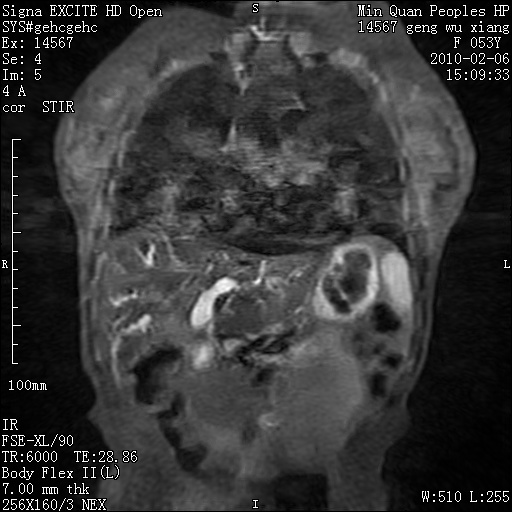

标题: MRI2762:胆道梗阻原因?

f,53y,全身黄染多日。

高位胆道梗阻 胆管癌可能性大

支持 高位胆道梗阻 胆管癌可能性大。